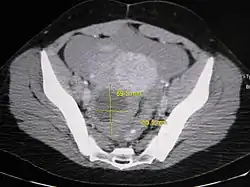

CT Ovarian Cyst

Further work up involves imaging, such as a pelvic ultrasound or CT scan.[7] Theca lutein cysts with diameters over 6 cm in size can be seen through these imaging modalities.[18] Benign ovarian cysts and complex cysts that are potentially malignant are distinguishable via ultrasounds.[19] Labs are also collected to evaluate leukocytes and tumor markers, such as beta-hCG and cancer antigen 125 (CA125).[20]